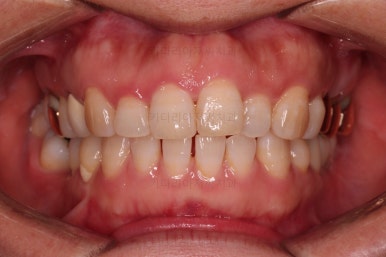

최종 사진을 보여드리겠습니다.

깔끔하게 마무리가 되었네요.

전후 비교입니다.

환자분도 치료에 만족하시어 미적으로 보기싫은 다른 금니들도 하나씩 교체하고 계신 중입니다.